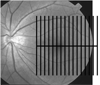

Methods: The RTVue FD-OCT system was used to map the macula over a 7 x 6 mm region. The macular OCT images were exported for automatic segmentation using software we developed. The program measured macular retinal (MR) thickness and GCC thickness. The GCC was defined as the combination of nerve fiber, ganglion cell, and inner plexiform layers. Pattern analysis was applied to the GCC map and the diagnostic powers of pattern-based diagnostic parameters were investigated. Results were compared with time-domain (TD) Stratus OCT measurements of MR and circumpapillary nerve fiber layer (NFL) thickness.